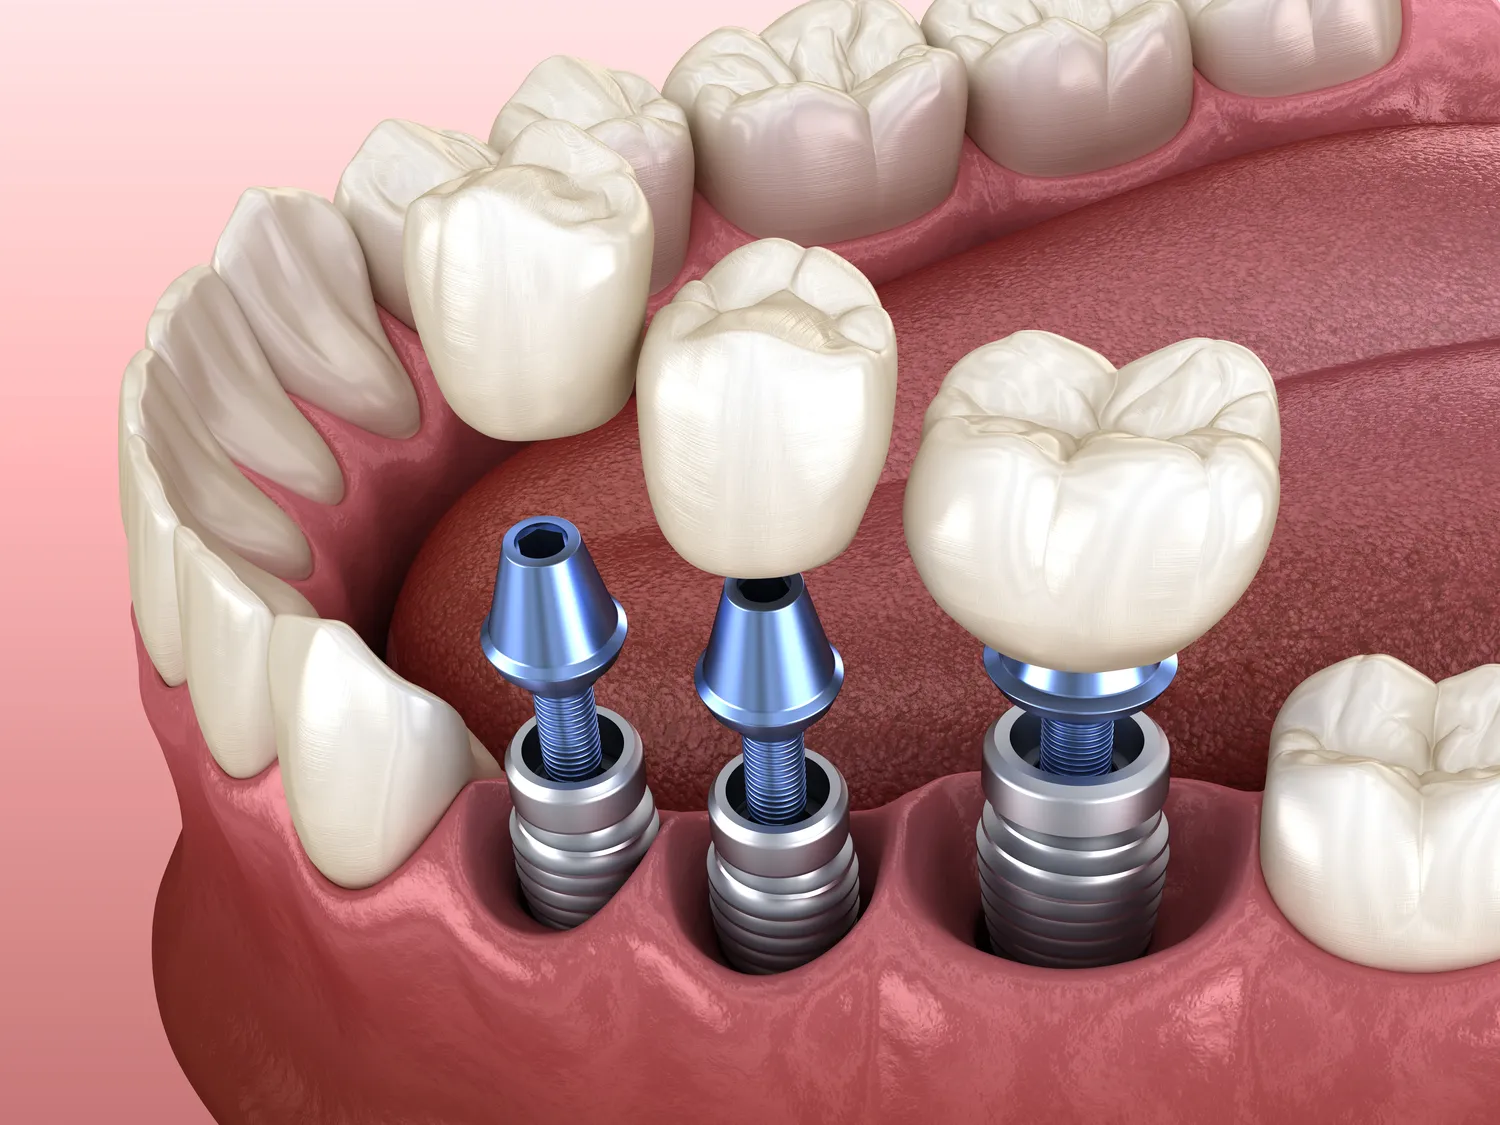

Jakie są etapy procesu wszczepienia implantów zębów

Proces wszczepienia implantów zębów składa się z kilku kluczowych etapów, które wymagają staranności i precyzji ze strony specjalisty. Pierwszym krokiem jest dokładna diagnostyka, która obejmuje badania obrazowe, takie jak tomografia komputerowa, oraz szczegółowy wywiad medyczny. Na tym etapie lekarz ocenia stan zdrowia pacjenta oraz jakość tkanki kostnej, co pozwala na podjęcie decyzji o dalszych krokach. Następnie, jeśli pacjent kwalifikuje się do zabiegu, przeprowadza się procedurę wszczepienia implantu. W trakcie tego etapu chirurg wykonuje niewielkie nacięcie w dziąśle i umieszcza implant w kości szczęki lub żuchwy. Po zakończeniu zabiegu pacjent otrzymuje zalecenia dotyczące pielęgnacji rany oraz ewentualnych leków przeciwbólowych. Kolejnym kluczowym etapem jest proces osteointegracji, który trwa od kilku tygodni do kilku miesięcy. W tym czasie implant łączy się z kością, co jest niezbędne dla jego stabilności. Po zakończeniu osteointegracji następuje etap mocowania korony protetycznej, która jest indywidualnie dopasowana do kształtu i koloru pozostałych zębów pacjenta.